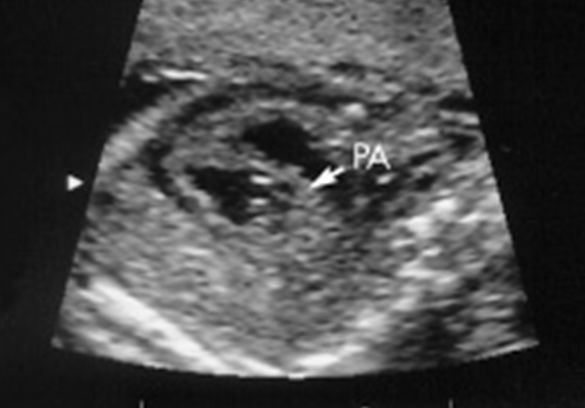

What view is this?

Short-axis Outflow Tract / RVOT

What vessels are seen?

What view is this and what vessels can be seen?

3 vessel view